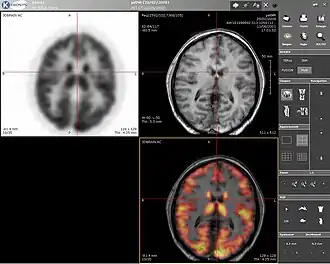

PET, MRI, and overlaid images of a human brain.

Positron emission tomography (PET) is a nuclear medicine imaging technique which produces a three-dimensional image or picture of functional processes in the body. The theory behind PET is simple enough. First a molecule is tagged with a positron emitting isotope. These positrons annihilate with nearby electrons, emitting two 511 keV photons, directed 180 degrees apart in opposite directions. These photons are then detected by the scanner, which can estimate the density of positron annihilations in a specific area. When enough interactions and annihilations have occurred, the density of the original molecule may be measured in that area. Typical isotopes include 11